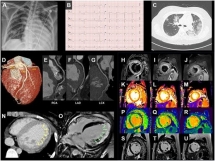

Ca bệnh điển hình chứng tỏ ngoài phổi, COVID-19 còn tổn hại tới tim

Hàn Quốc công bố một bệnh nhân mắc COVID-19 đầu tiên có phát bệnh về tim vào cuối tuần qua. Thông tin cho thấy virus SARS-CoV-2 thường gây bệnh liên quan tới hô hấp có ...